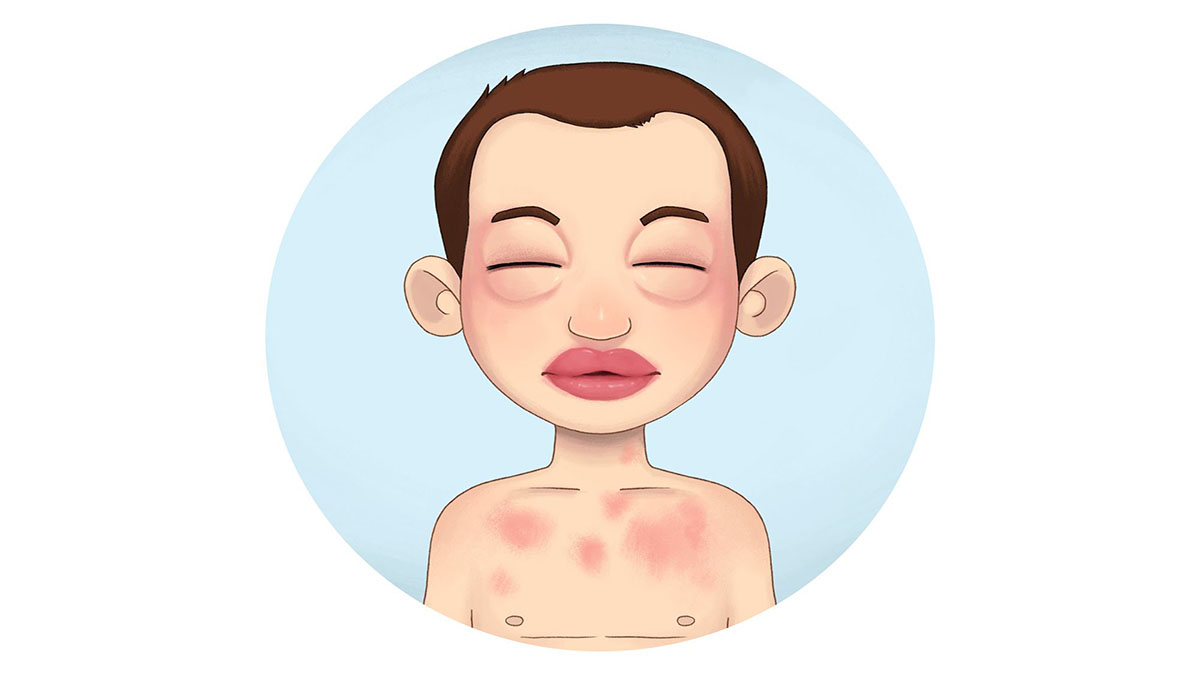

قیمت: 88٬000 تومان - دسته بندی فایل: علوم پزشکیپاورپوینت شوک و آنافیلاکسی 60 اسلاید

فروش ویژه فایل های پاورپوینت حرفه ای شوک و آنافیلاکسی با تخفیف استثنایی - دسته بندی : پاورپوینت نوع فایل : powerpoint (..ppt) ( قابل ویرایش و آماده پرینت ) تعداد اسلاید : 60 اسلاید

قیمت: 42٬000 تومان - دسته بندی فایل: علوم پزشکیپاورپوینت فوریتهای پزشکی در کودکان

فروش ویژه پاورپوینت حرفه ای فوریتهای پزشکی در کودکان با تخفیف استثنایی فقط 47 هزار تومان تعداد اسلاید: 20 اسلاید